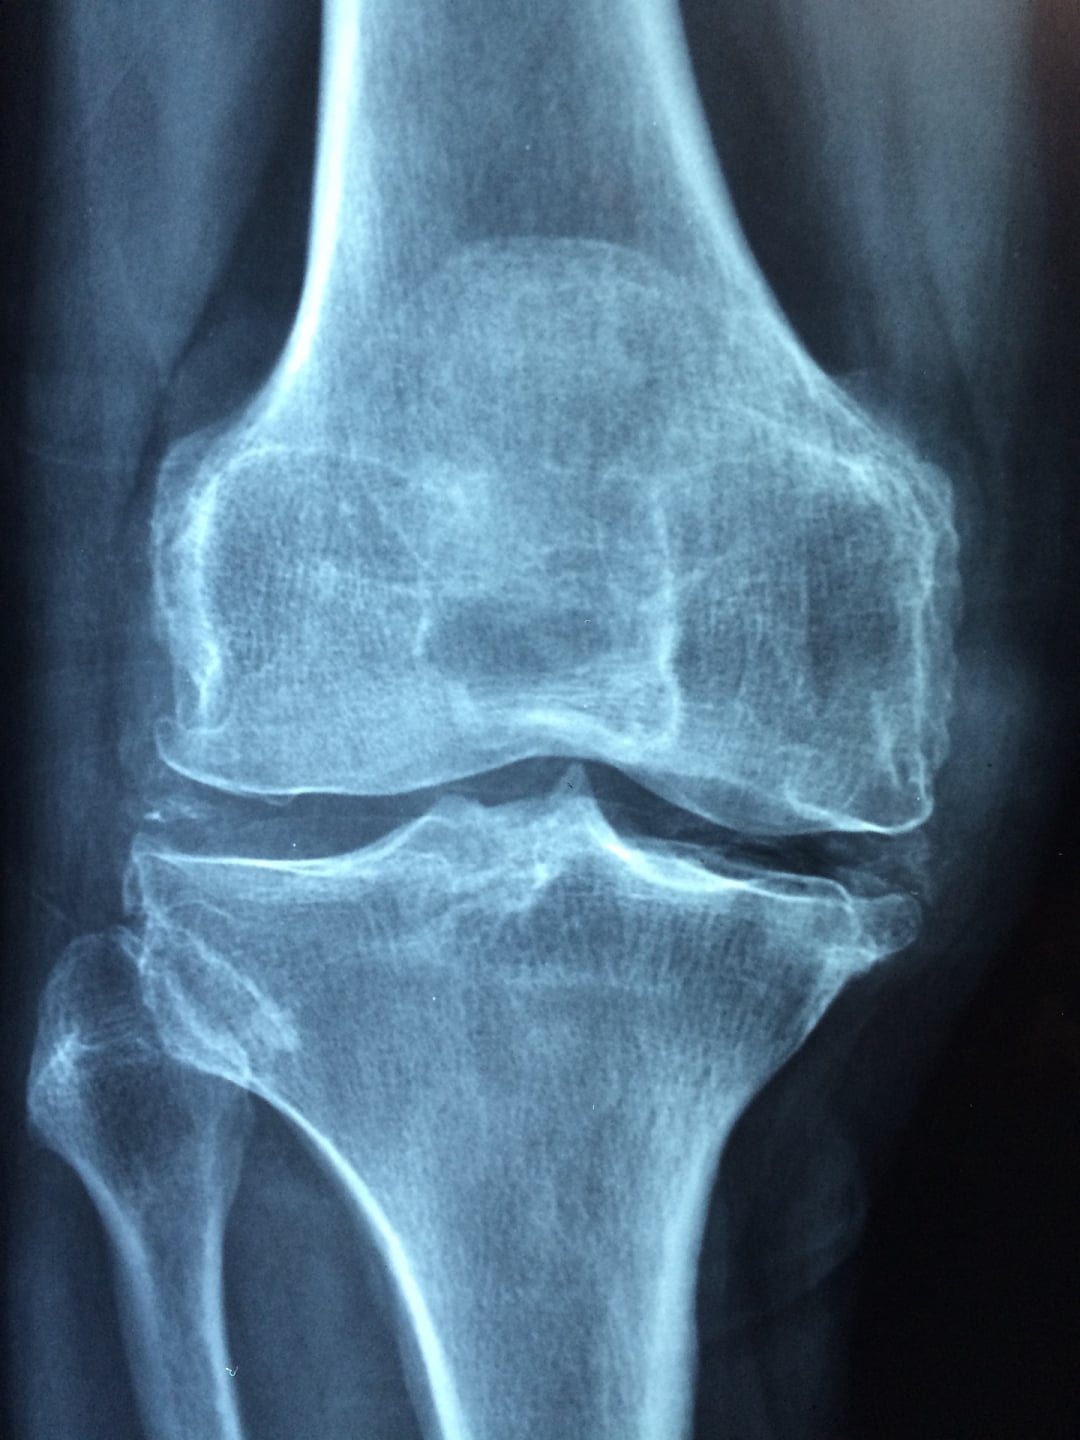

A Box Medical által kínált sarokcsonton végzett DEXA (Dual-Energy X-ray Absorptiometry) vizsgálat innovatív és megbízható módszert kínál az osteoporózis diagnosztizálására és kezelésére. Ez a modern technológia kritikus szerepet játszik a csontsűrűség pontos mérésében, lehetővé téve az orvosok számára, hogy időben felismerjék a csontok gyengülését, és megelőzzék a törések kialakulását.

A DEXA vizsgálat jelentősége az osteoporózis kezelésében vitathatatlan. Az osteoporózis egy olyan állapot, amely a csontok tömegének és sűrűségének csökkenésével jár, növelve ezzel a törések kockázatát. A korai felismerés és kezelés kulcsfontosságú a betegség súlyosbodásának megelőzésében és a betegek életminőségének javításában. A Box Medical által kínált DEXA vizsgálat éppen ezt a célkitűzést szolgálja.

A DEXA vizsgálat előnyei számosak. Először is, a vizsgálat gyors és fájdalommentes, ami kényelmes megoldást kínál a betegek számára. Másodszor, rendkívül pontos, lehetővé téve a legkisebb csontsűrűség-változások azonosítását is. Harmadszor, a sarokcsonton végzett vizsgálat különösen előnyös, mivel a sarokcsont sűrűsége jó indikátora lehet a teljes csontrendszer állapotának.

A Box Medical technológiája kiemelkedik a magas szintű pontossággal és megbízhatósággal. A cég által használt modern DEXA készülékek lehetővé teszik az orvosok számára, hogy részletes képet kapjanak a csontsűrűségről, ami alapján személyre szabott kezelési tervet állíthatnak össze. Ez a személyre szabott megközelítés biztosítja, hogy a betegek a legmegfelelőbb kezelést kapják, figyelembe véve egyedi egészségi állapotukat és kockázataikat.

Az osteoporózis megelőzése és kezelése hosszú távú elkötelezettséget igényel mind a betegek, mind az egészségügyi szolgáltatók részéről. A Box Medical által kínált sarokcsonton végzett DEXA vizsgálat kulcsfontosságú eszköz ebben a folyamatban. A vizsgálat segítségével az orvosok képesek lesznek a csontsűrűség pontos mérésére és a csontvesztés korai felismerés

ére, ami lehetővé teszi az időben történő beavatkozást és a súlyos törések megelőzését.

Összefoglalva, a Box Medical által kínált sarokcsonton végzett DEXA vizsgálat egy olyan előremutató technológia, amely jelentős előnyöket kínál az osteoporózis diagnosztizálásában és kezelésében. A vizsgálat gyorsasága, pontossága és a személyre szabott kezelési terv lehetősége hozzájárul a betegek életminőségének javításához és a törések kockázatának csökkentéséhez. A Box Medical elkötelezettsége az innováció és a páciensek támogatása mellett biztosítja, hogy a sarokcsonton végzett DEXA vizsgálat valóban hatékony eszköz legyen az osteoporózis kezelésében.